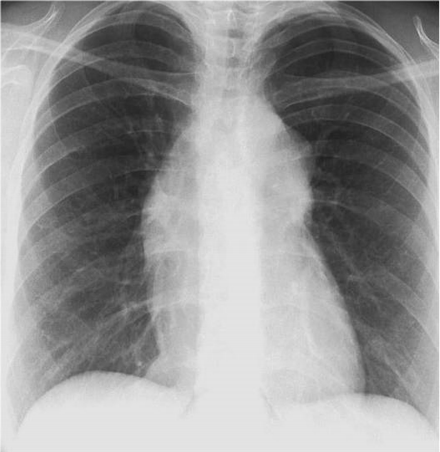

和X线胸片见图27-1和图27-2。除CK、CK-MB和TNI升高外,其他实验室检查均正常。

图27-2 患者胸片

显性遗传疾病,但他没有家族史,大约1/3的马方综合征是由原纤维蛋白1(FBN1)基因突变引起的,因而可无家族史。体检提示有A型主动脉夹层并发症,两上肢之间的血压无差别是因为夹层起源于升主动脉并累及右头臂干和左锁骨下动脉,胸片显示纵隔增宽。此外,患者存在下壁ST段抬高心肌梗死提示夹层累及右冠状动脉开口,伴有急性主动脉瓣闭合不全和下壁心肌梗死引起的急性心衰